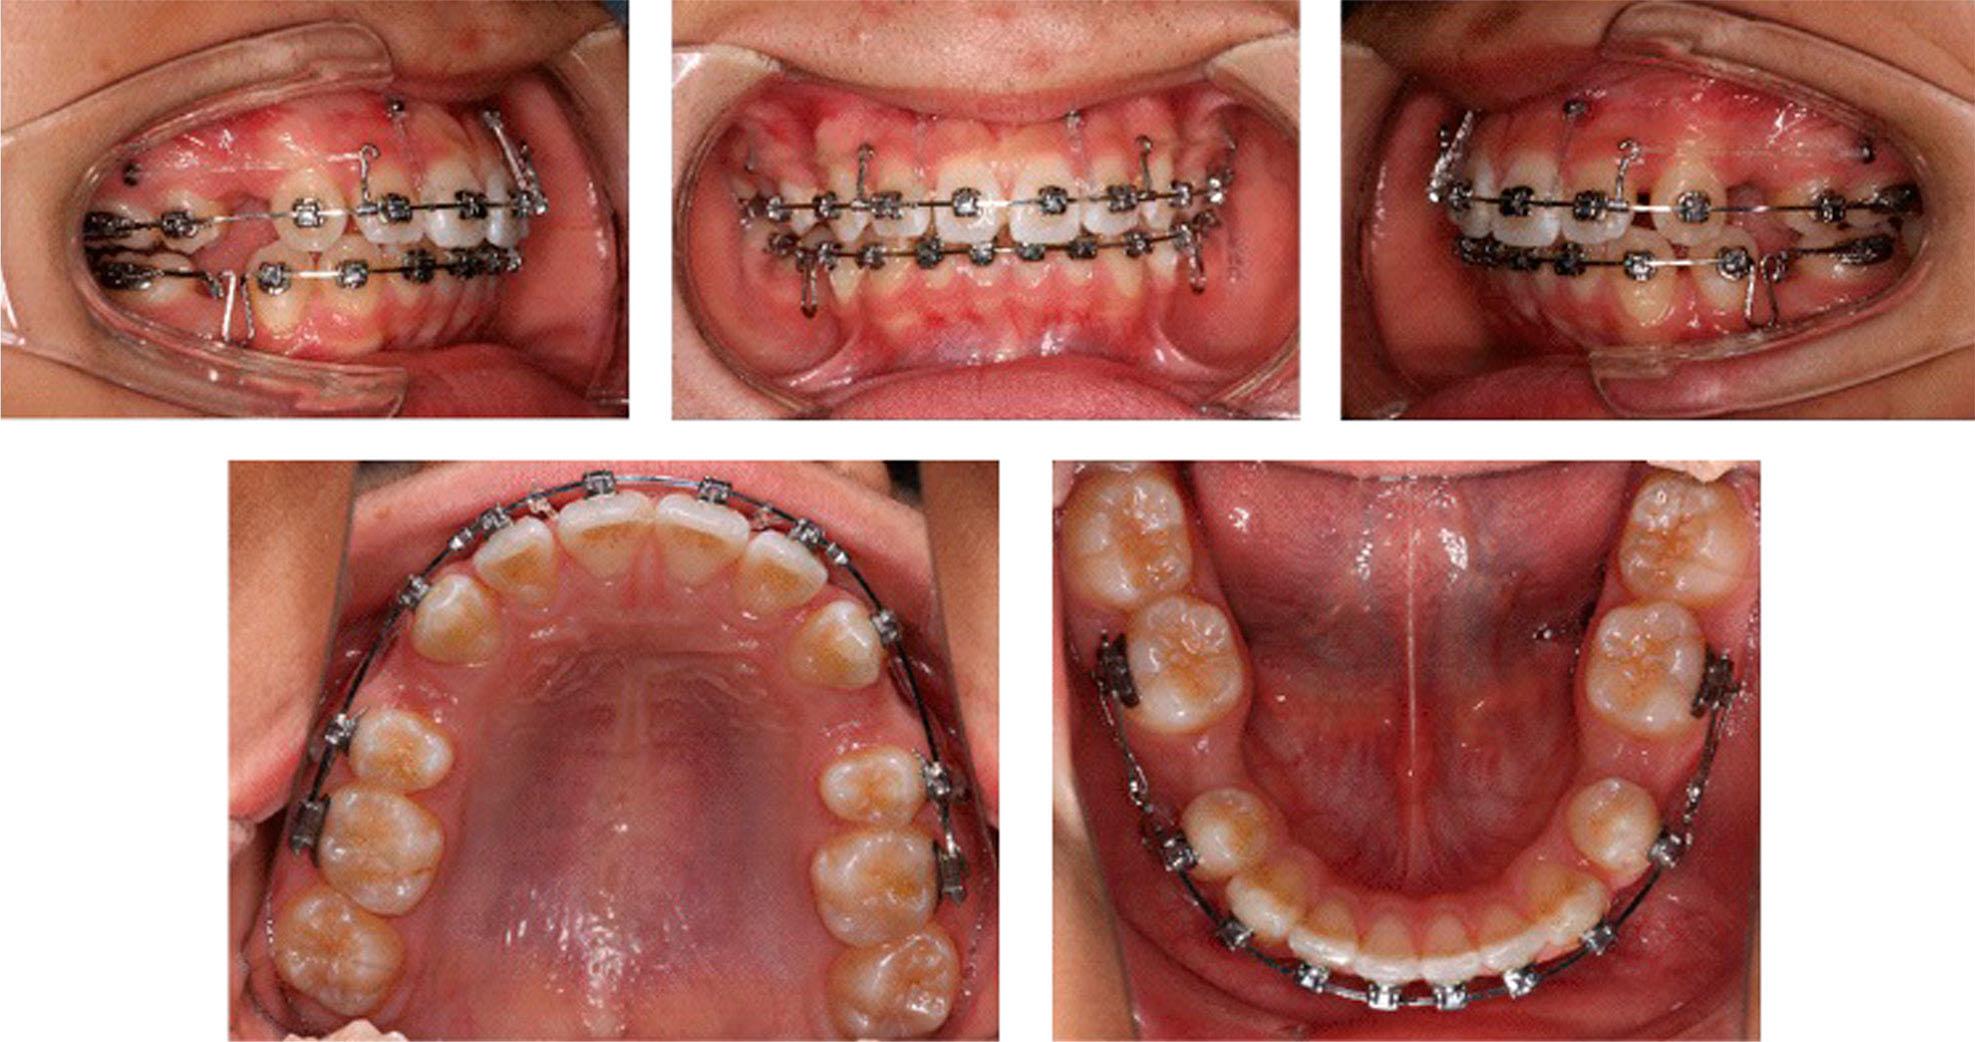

Cephalometric measurements (T1 Pretreatment; T2 12 months after Twin-block treatment; T3 36 months after fixed orthodontic treatment)

| Measurement | Norm | T1 | T2 | T3 |

|---|---|---|---|---|

| SNA(°) | 83.0 | 87.3 | 86.8 | 86.1 |

| SNB(°) | 80.0 | 77.9 | 79.6 | 81.6 |

| ANB(°) | 3.0 | 9.4 | 7.2 | 4.5 |

| NP-FH(°) | 85.0 | 81.5 | 84.5 | 84.4 |

| NA-PA(°) | 6.0 | 19.8 | 16.5 | 10.0 |

| U1-SN(°) | 105.0 | 108.8 | 101.3 | 107.9 |

| U1-NA(°) | 22.0 | 21.6 | 14.5 | 21.9 |

| L1-NB(°) | 30.0 | 37.3 | 41.4 | 25.6 |

| IMPA(°) | 88.0 | 111.0 | 113.2 | 98.7 |

| FMIA(°) | 67.0 | 44.0 | 43.1 | 59.0 |

| FMA(°) | 25.0 | 25.0 | 23.7 | 22.3 |

| Y-axis angle (°) | 65.8 | 65.8 | 64.2 | 64.0 |

| Z-angle(°) | 75.0 | 52.8 | 59.7 | 65.3 |

| Po-Go(mm) | – | 6.9 | 7.2 | 7.3 |

| Gn-Co(mm) | – | 10.2 | 10.8 | 11.1 |